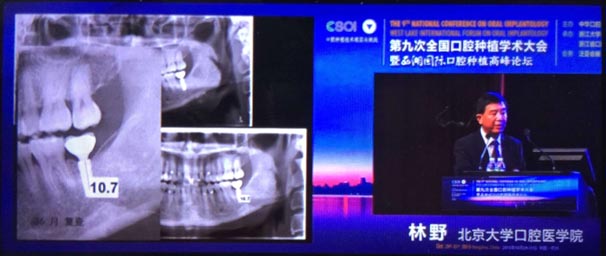

2015年10月29日第九次全國(guó)口腔種植學(xué)術(shù)大會(huì)暨“西湖國(guó)際”口腔種植高峰論壇在浙江省人民大會(huì)堂隆重開幕。這是中華口腔種植專業(yè)委員會(huì)主辦的兩年一度的全國(guó)性學(xué)術(shù)會(huì)議,代表了中國(guó)口腔種植學(xué)發(fā)展的水平和方向。

會(huì)議期間國(guó)內(nèi)知名口腔專家針對(duì)當(dāng)前口腔種植領(lǐng)域熱點(diǎn)進(jìn)行了精彩的學(xué)術(shù)演講。其中北京大學(xué)口腔醫(yī)學(xué)院林野教授的演講主題是“種植體設(shè)計(jì)及臨床意義”。

威高演講中林野教授對(duì)國(guó)產(chǎn)品牌WEGO牙種植體系統(tǒng)的設(shè)計(jì)和臨床表現(xiàn)表示肯定,向在座觀眾展示了WEGO牙種植體系統(tǒng)的臨床病例。病例對(duì)76枚WEGO牙種植體進(jìn)行了平均21個(gè)月的追蹤觀察,結(jié)果表明WEGO牙種植體脫落、松動(dòng)、種植體周圍病現(xiàn)象均為0,頸部骨吸收平均值為0.20mmSD值0.07。